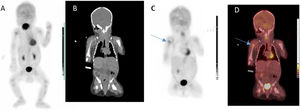

Given the worsening symptoms and with the aim of assessing for the potential presence of additional foci of infection, a whole-body positron-emission tomography (PET)/computed tomography (CT) scan was performed (Biograph™ mCT 20 scanner, Siemens Medical Systems; Knoxville, TN, USA), including the extremities (Fig. 1), with an administered activity of 36.8 MBq/0.99 mCi of 18F-fluorodeoxyglucose (18F-FDG) (paediatric dose recommended by the European Association of Nuclear Medicine)1 and low-dose CT-based attenuation correction (80 kVp, 5 mAs).

(A) Maximum intensity projection image. (B) Coronal CT image. (C) Coronal PET image. (D) Coronal PET/CT fusion image: 18F-FDG imaging with high uptake in the proximal epiphysis of the right humerus (blue arrow) associated with active osteomyelitis2 and moderate uptake in the articular surface of the right humeral head associated with the already established active articular illness.